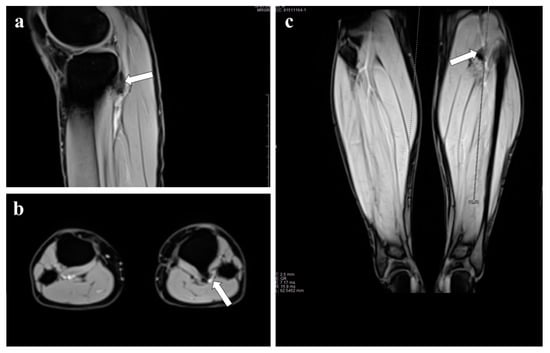

3. Representative Explanatory Case

| Present case | 1 | AI | Tibia | Thrombolytic Therapy | 34 | Solitary |